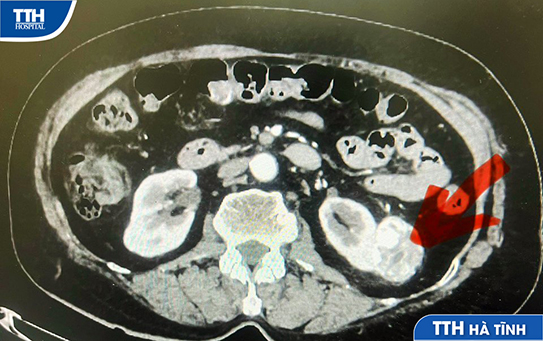

Ông B.Đ.C (70 tuổi, trú tại Hà Tĩnh) đau tức ngực, khó thở một tháng nay. Đến thăm khám sức khỏe định kỳ tại BVĐK TTH Hà Tĩnh phát hiện có những nốt tổn thương nhỏ ở phổi theo dõi u phổi. Kích thước nốt lớn nhất là 15 mm.

✔ Sau đó, các bác sĩ Khoa Ung bướu đã tiến hành sinh thiết u phổi xuyên thành ngực, dưới hướng dẫn của Chụp CLVT định vị chính xác vị trí u và bấm mẫu. Kết quả xác định bệnh nhân ung thư biểu mô tuyến của phổi.